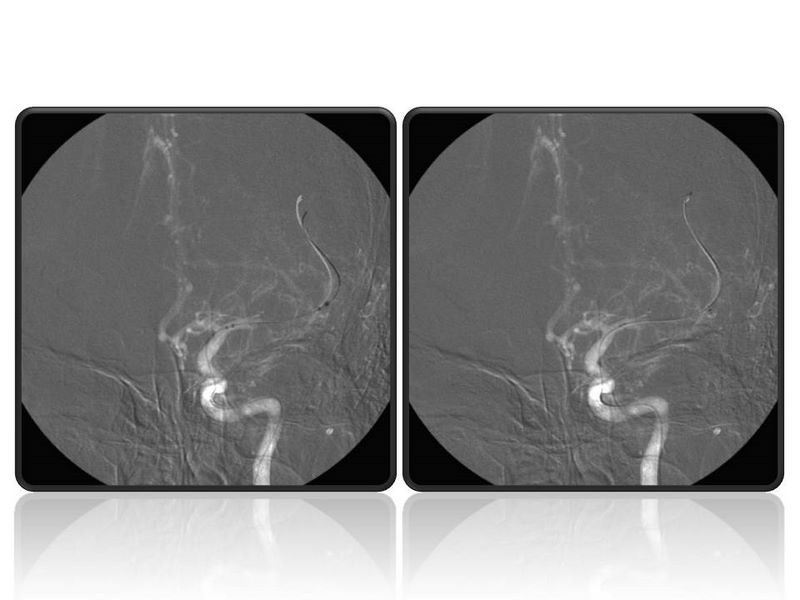

Ictus con stent